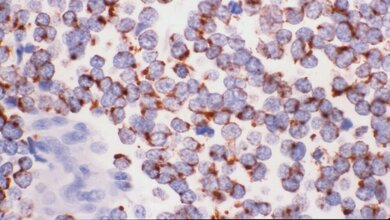

„Wir konnten zeigen, dass diese Zellen einen Botenstoff ins Blut abgeben, der wiederum Immunzellen anlockt.* Diese wandern dann über die Milz in die Pleurahöhle ein und verursachen dort die Flüssigkeitsansammlung“, erklärt Studienleiter Stathopoulos den Mechanismus. Zusätzlich fanden die Wissenschaftler die KRAS mutierten Krebszellen in MPE-Material von Lungenkrebspatienten sowie in Zelllinien, die davon abgeleitet worden waren.

Um zu überprüfen, ob das neu gewonnene Wissen in der Praxis angewendet werden könnte, testeten die Forscher zwei Wirkstoffe, die den Mechanismus an zwei verschiedenen Stellen unterbrechen: Im Versuchsmodell konnten sie zeigen, dass sowohl der KRAS Inhibitor Deltarasin** als auch ein Antiköper gegen den von den Krebszellen ausgesandten Botenstoff dem Pleuraerguss entgegenwirkten.